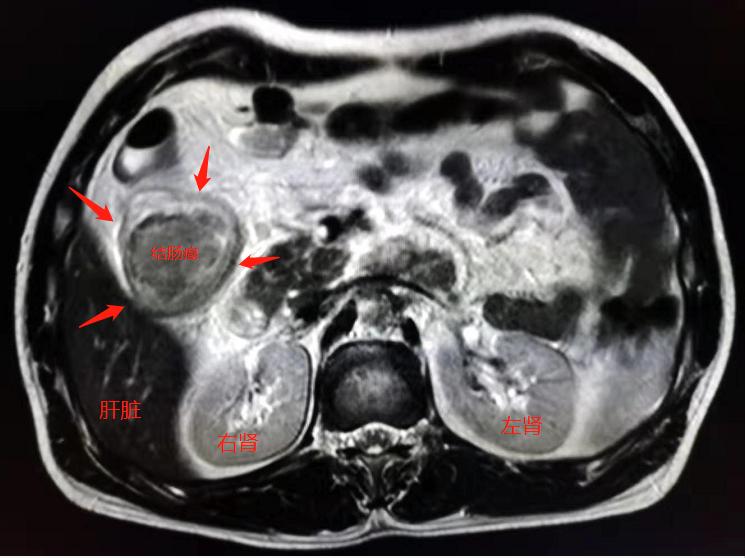

来医院全面检查后发现了右侧结肠癌:

还好,没有发现明显转移,及时做了根治手术。